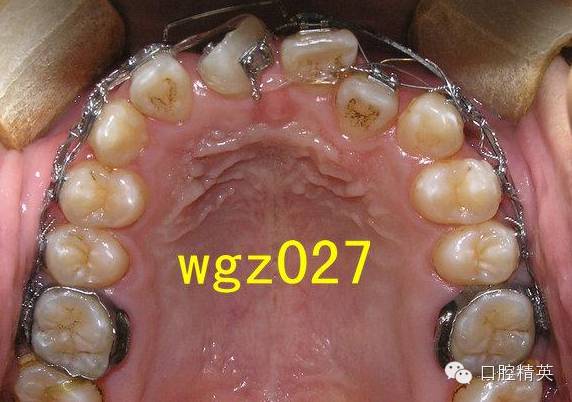

这是作者经手矫治的一位16岁男孩,牙列拥挤,磨牙远中关系,上颌中切牙(UR1)严重扭转案例。矫治前期使用了磨牙推进器推后矫治技术,开拓后牙弓间隙,调整磨牙关系。

本篇内容主要介绍该患者2期治疗阶段,上颌严重扭转中切牙经典矫治过程,希望对年轻医生,进修医生的学习及临床工作有所借鉴和帮助。